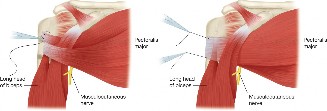

The correct answer is (A). In young, active patients with a massive, irreparable rotator cuff tear without glenohumeral arthritis, a tendon transfer is the most reasonable option to attempt to restore function of the shoulder. In a tear involving the supraspinatus and infraspinatus, the posterior and inferior force-couples in the transaxial and coronal planes, respectively, are out of balance because of the involvement of the infraspinatus in both of those. Because of this, the humerus cannot be dynamically stabilized in the glenoid during active movement of the shoulder. The most popular way to restore this in a young, healthy patient is through a latissimus dorsi tendon transfer in which the insertion of the tendon is transferred from the humeral shaft to the greater tuberosity (see Fig. 2–19). This creates a new posterior and inferior force-couple and creates an external rotation force.

Figure 2–19_Latissimus dorsi tendon transfer on a right shoulder viewed from superiorly with anterior being the left side of the image. Top: final appearance. Bottom: final sutures being thrown through the latissimus dorsi. (From Omid R, Lee B. Tendon transfers for irreparable rotator cuff tears. _J Am Acad Orthop Surg. 2013;21(8):492–501.)

It should be noted that due to the differences in the length and force vector magnitude and direction between the infraspinatus and latissimus dorsi, the force couple is not perfectly restored, and thus the shoulder after a tendon transfer never works as well as with a successful repair of the native cuff. The latissimus force vector is much more vertical and greater in magnitude than the infraspinatus. This transfer thus has variable results in restoring function. Factors associated with poor outcome include subscapularis dysfunction, deltoid dysfunction, osteoarthritis of the glenohumeral or acromioclavicular joint, and loss of teres minor function, none of which are present in this patient.

The correct answer is (C). When the native rotator cuff is irreparable, using a tendon transfer is the next step. Since the force vector of the pectoralis major muscle is similar to that of the subscapularis, this tendon can be used as an effective tendon transfer, restoring internal rotation and humeral head centering and compression. The surgery is performed by detaching the pectoralis major from its humeral insertion and moving the insertion to the lesser tuberosity. The tendon of

the pectoralis major can run anterior to the conjoined tendon or can be transposed posterior to the conjoined tendon but anterior to the musculocutaneous nerve. This latter method more closely replicates the force vector direction of the subscapularis, but has not been shown to lead to better outcomes (see Fig. 2–20). A latissimus dorsi tendon transfer is also sometimes used for irreparable subscapularis tendon tears.

Figure 2–20_Pectoralis major tendon transfer. Left: partial tendon transfer. Right: complete tendon transfer. Both use a subcoracoid approach. (From Omid R, Lee B. Tendon transfers for irreparable rotator cuff tears. _J Am Acad Orthop Surg. 2013;21(8):492–501.)